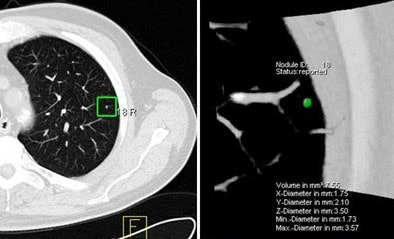

![]() |

| The marked nodule (green) was deemed not clinically relevant. However, CAD detected it only at the full-dose setting, and not at low-dose (10 mAs). Image courtesy of Dr. Marco Das. |